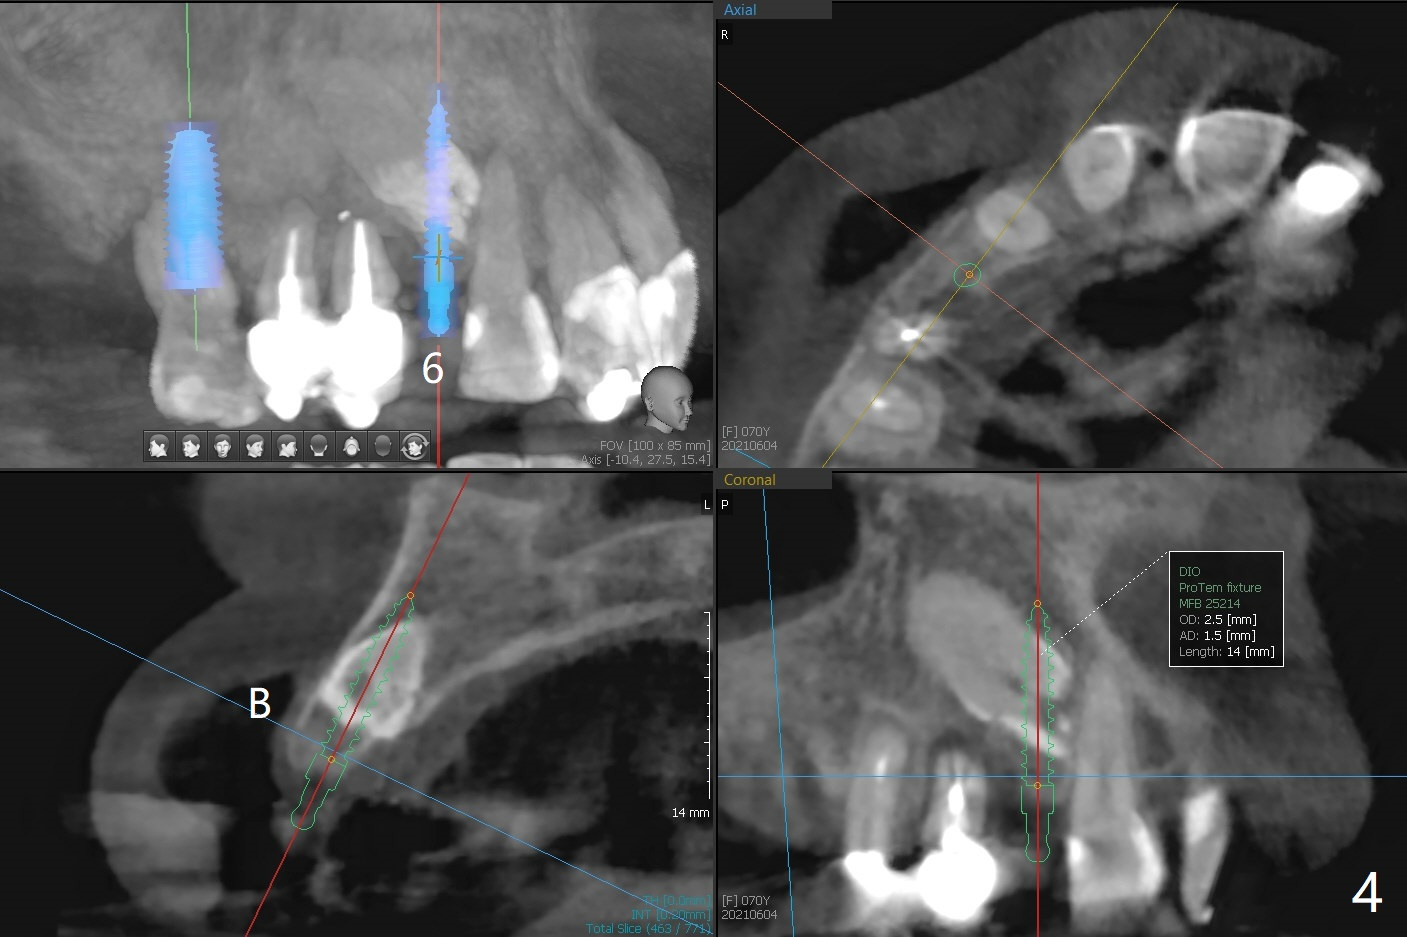

A 70-year-old woman requests implants at #3 and 5 because of bone loss (Fig.1). Since the impacted tooth #6 crosses the trajectory of the implant at #5, extraction of the former is necessary (Fig.2). Palatal bone loss is severe at #5, a 3.5x15 mm 1-piece implant will be placed slightly more buccal than what is shown for 4x13 mm 2-piece one at Fig.2. A 5x11.5 mm implant will be placed at #3 without sinus lift (Fig.3). In fact the patient is concerned about cleasenability of the cantilever bridge. One-piece implant will be placed if needed (Fig.4).